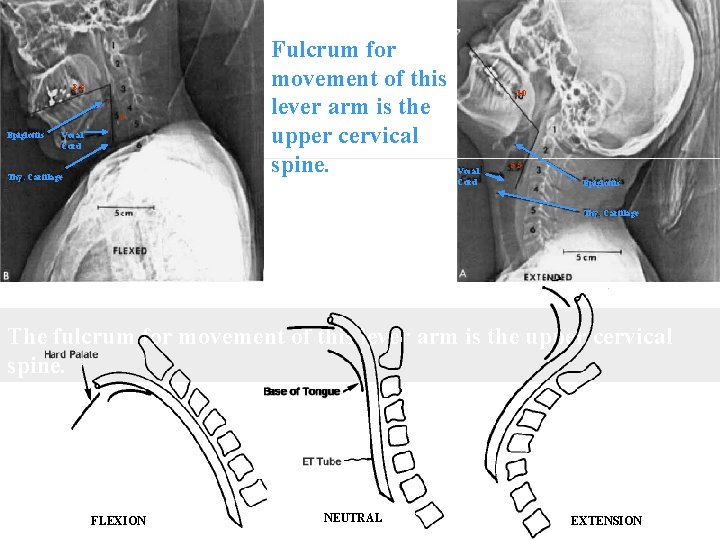

8. 3 5 Epiglottis Vocal Cord Thy. Cartilage Fulcrum for movement of this lever arm is the upper cervical spine. . 10 Vocal Cord 5. 5 Epiglottis Thy. Cartilage The fulcrum for movement of this lever arm is the upper cervical spine. FLEXION NEUTRAL EXTENSION